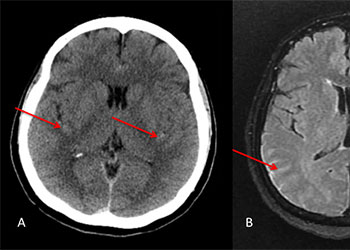

The subararachnoid hemorrhage was focused primarily within the spinal axis of the cervical thoracic and lumbar spine with secondary extension into the brain. A suspicious focal hematoma or mass was observed within the left T4-T5 region with local mass effect representing an intradural extra medullary abnormality with secondary compression of the cord and central myelopathic T2 signal abnormality (Figure 2. A,B,C,D).

Figure 2: A) T1 B) C+ T1 C) STIR D) FS C+ T1 demonstrate focal hemorrhage, contrast enhancement, mass effect, and myelopathic cord signal at T4 (arrows)